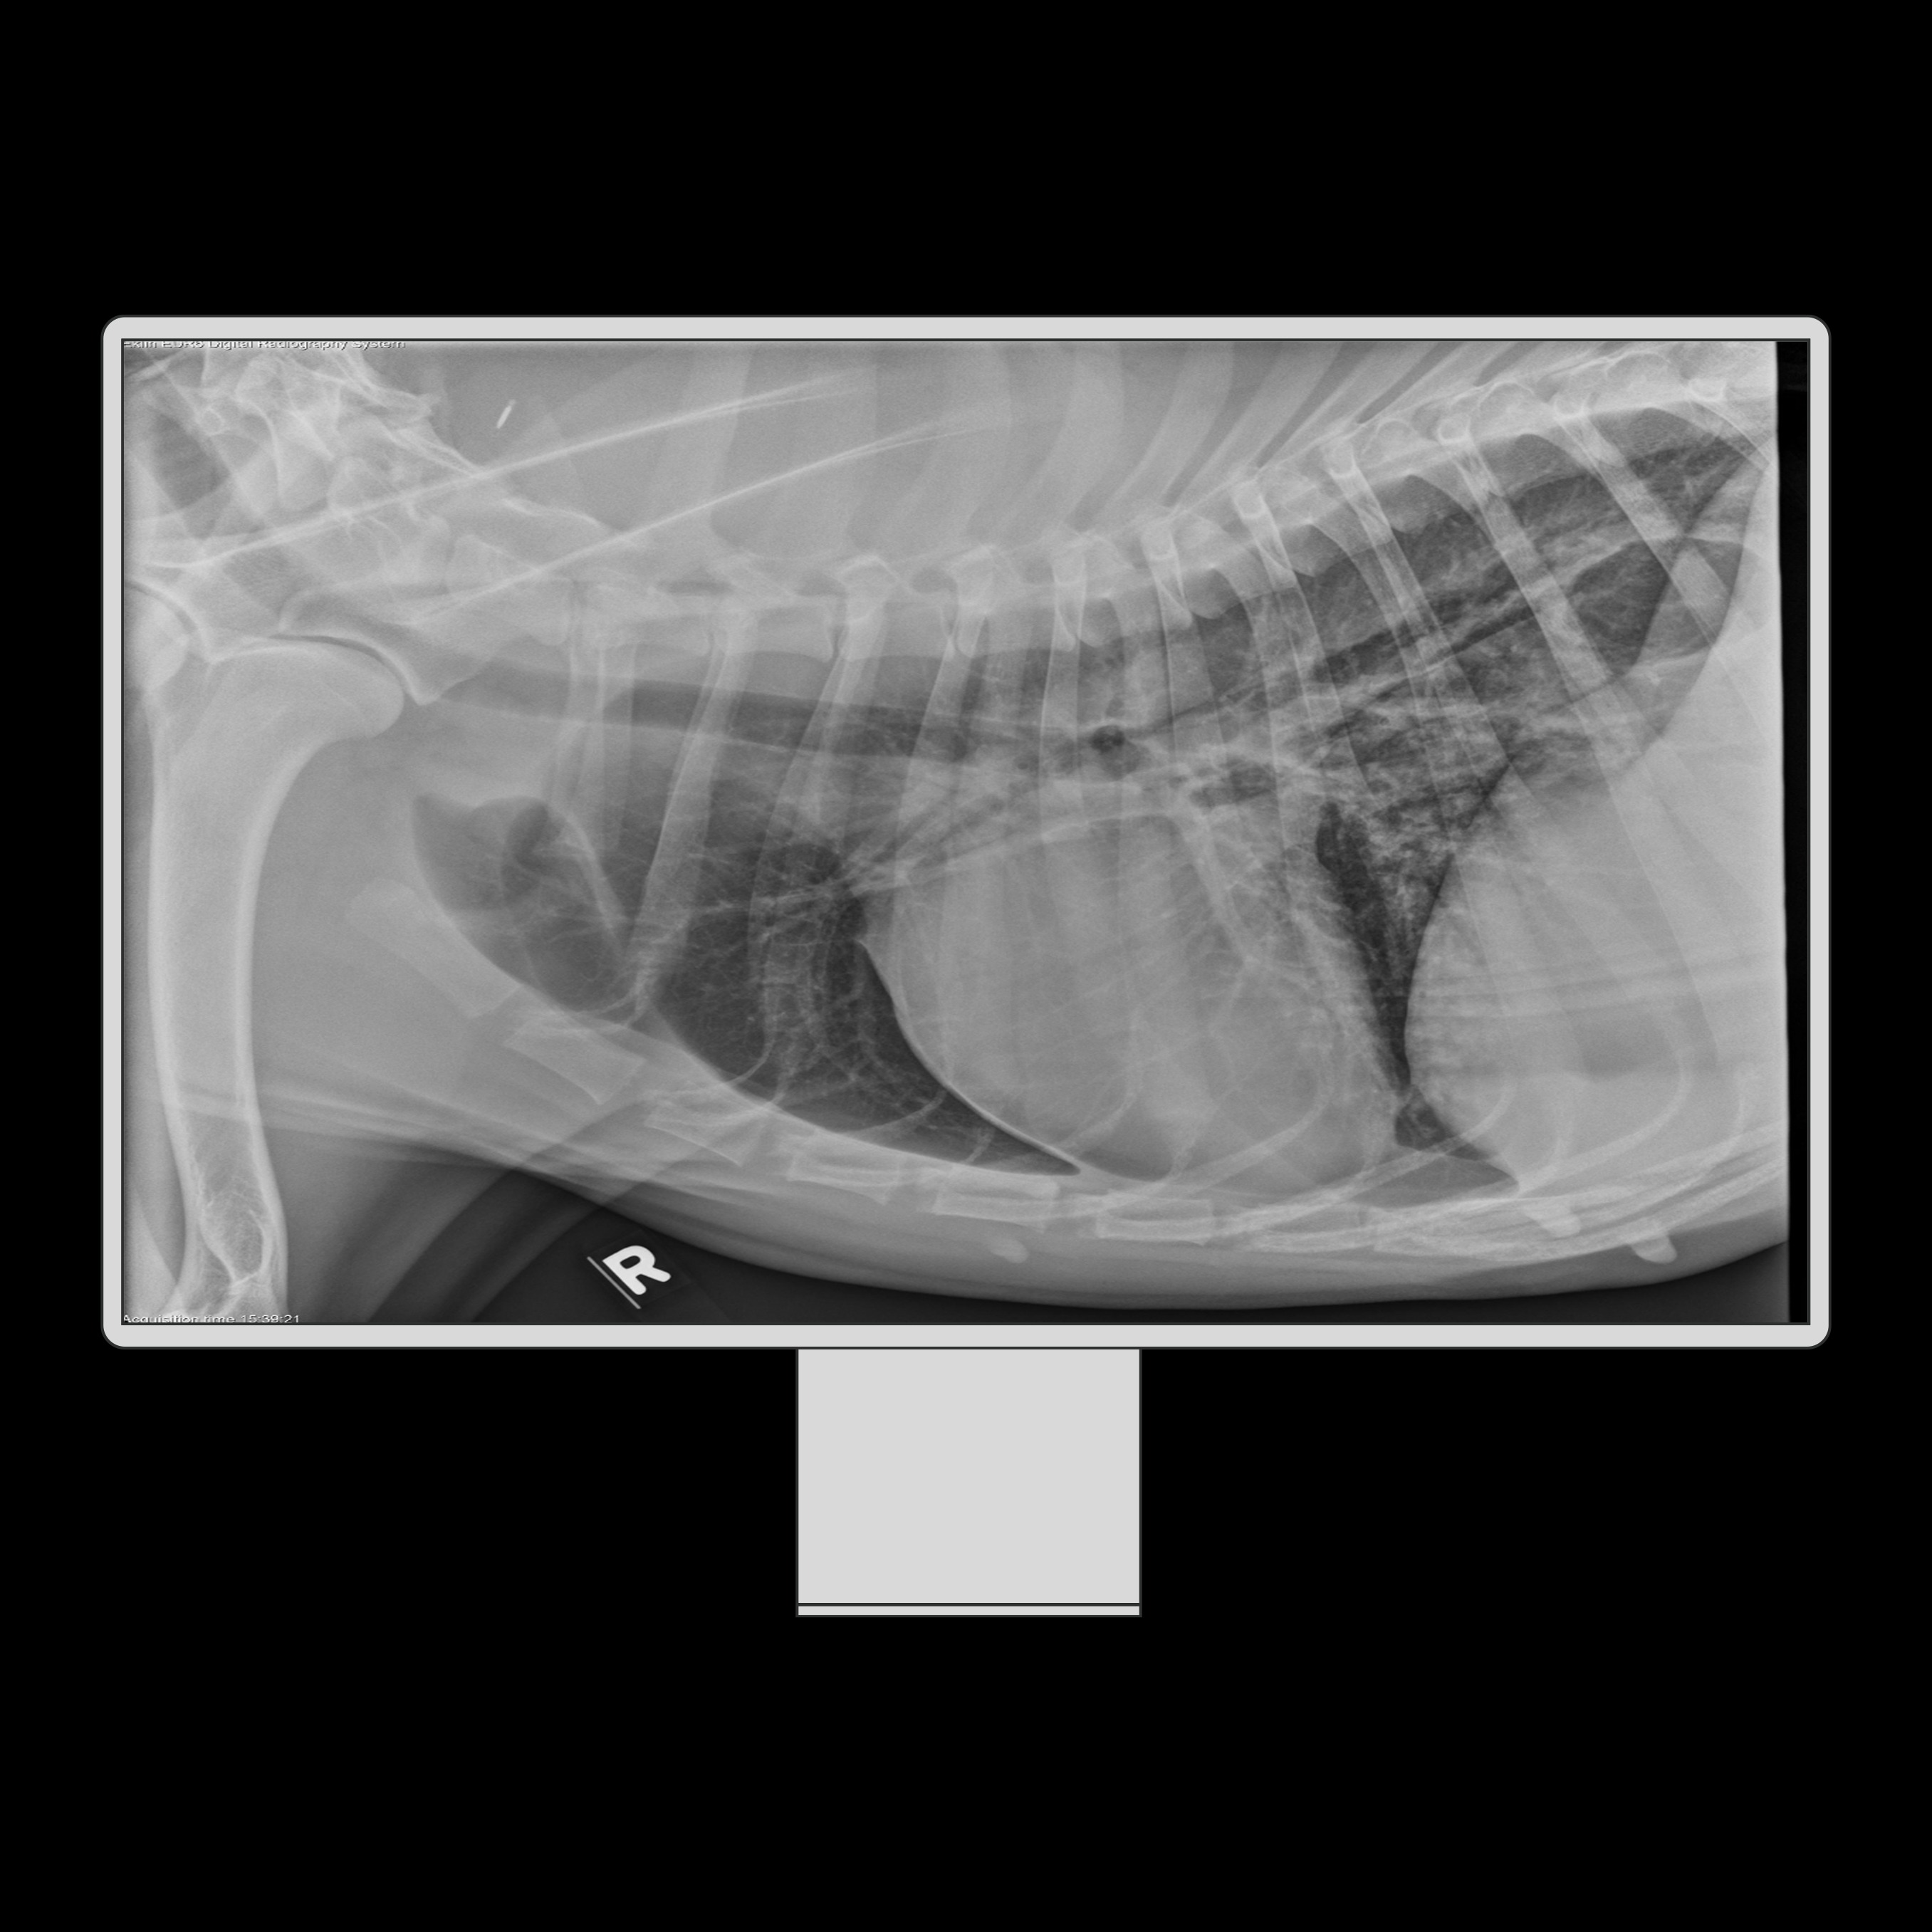

Human diseased Chest XRay Image, showing patient with fieldpen, health Chest X Ray Missed Cancer In 90% of the cases, errors in diagnosis of lung. Chest radiographs (cxrs) are the most frequently ordered imaging study for numerous clinical indications. In 90% of the cases, errors. Missed lung cancer is a source of concern among radiologists and an important medicolegal challenge. Although ct is much more sensitive than chest radiography, lung cancer may. Missed lung cancer. Chest X Ray Missed Cancer.

Common features of missed lung cancer on chest Xray Chest X Ray Missed Cancer In 90% of the cases, errors in diagnosis of lung. Missing lesions on chest radiographs is frequent and the largest source of medicolegal issues. This special features article discusses and provides examples of commonly missed cxr findings of clinical significance. Missed lung cancer is a source of concern among radiologists and an important medicolegal challenge. The increased clinical demand on. Chest X Ray Missed Cancer.

A chest xray of a patient with lung cancer showing a shadow on the Chest X Ray Missed Cancer Missing lesions on chest radiographs is frequent and the largest source of medicolegal issues. The incidence, principal causes, and potential adverse consequences. In this chapter, we report reasons for missing lesions, we distinguish perception and. Missed lung cancer is a source of concern among radiologists and an important medicolegal challenge. Chest radiographs (cxrs) are the most frequently ordered imaging study. Chest X Ray Missed Cancer.